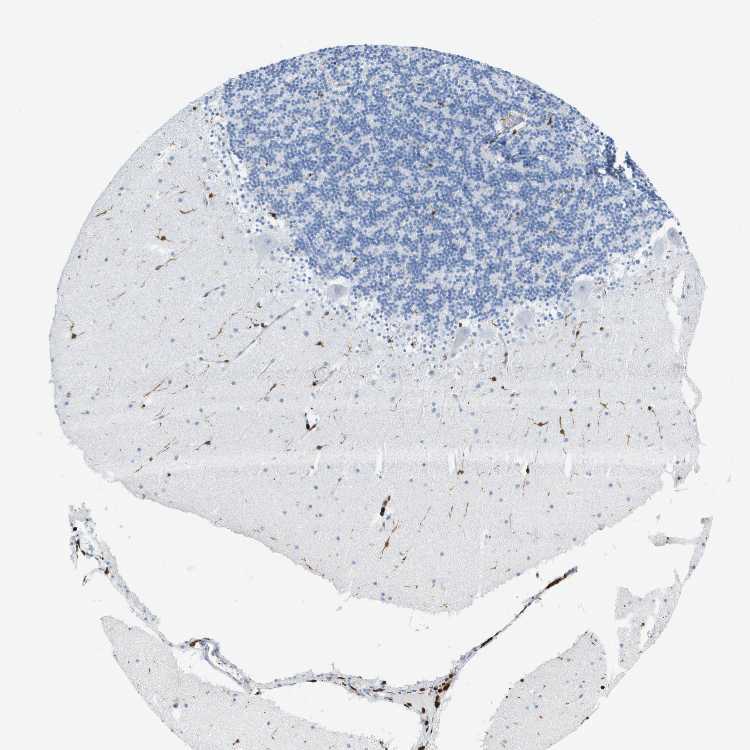

CEREBELLUM - Antibody stainingi

Antibody staining in the annotated cell types in the current human tissue is reported as not detected, low, medium, or high, based on conventional immunohistochemistry profiling in selected tissues. This score is based on the combination of the staining intensity and fraction of stained cells.

Each image is clickable and will lead to virtual microscopy that enables deeper exploration of all samples and also displays staining intensity scores, fraction scores and subcellular localization as well as patient and tissue information for each sample.

Antibody HPA017719

Purkinje cells Not detected

Cells in granular layer Not detected

Cells in molecular layer Medium